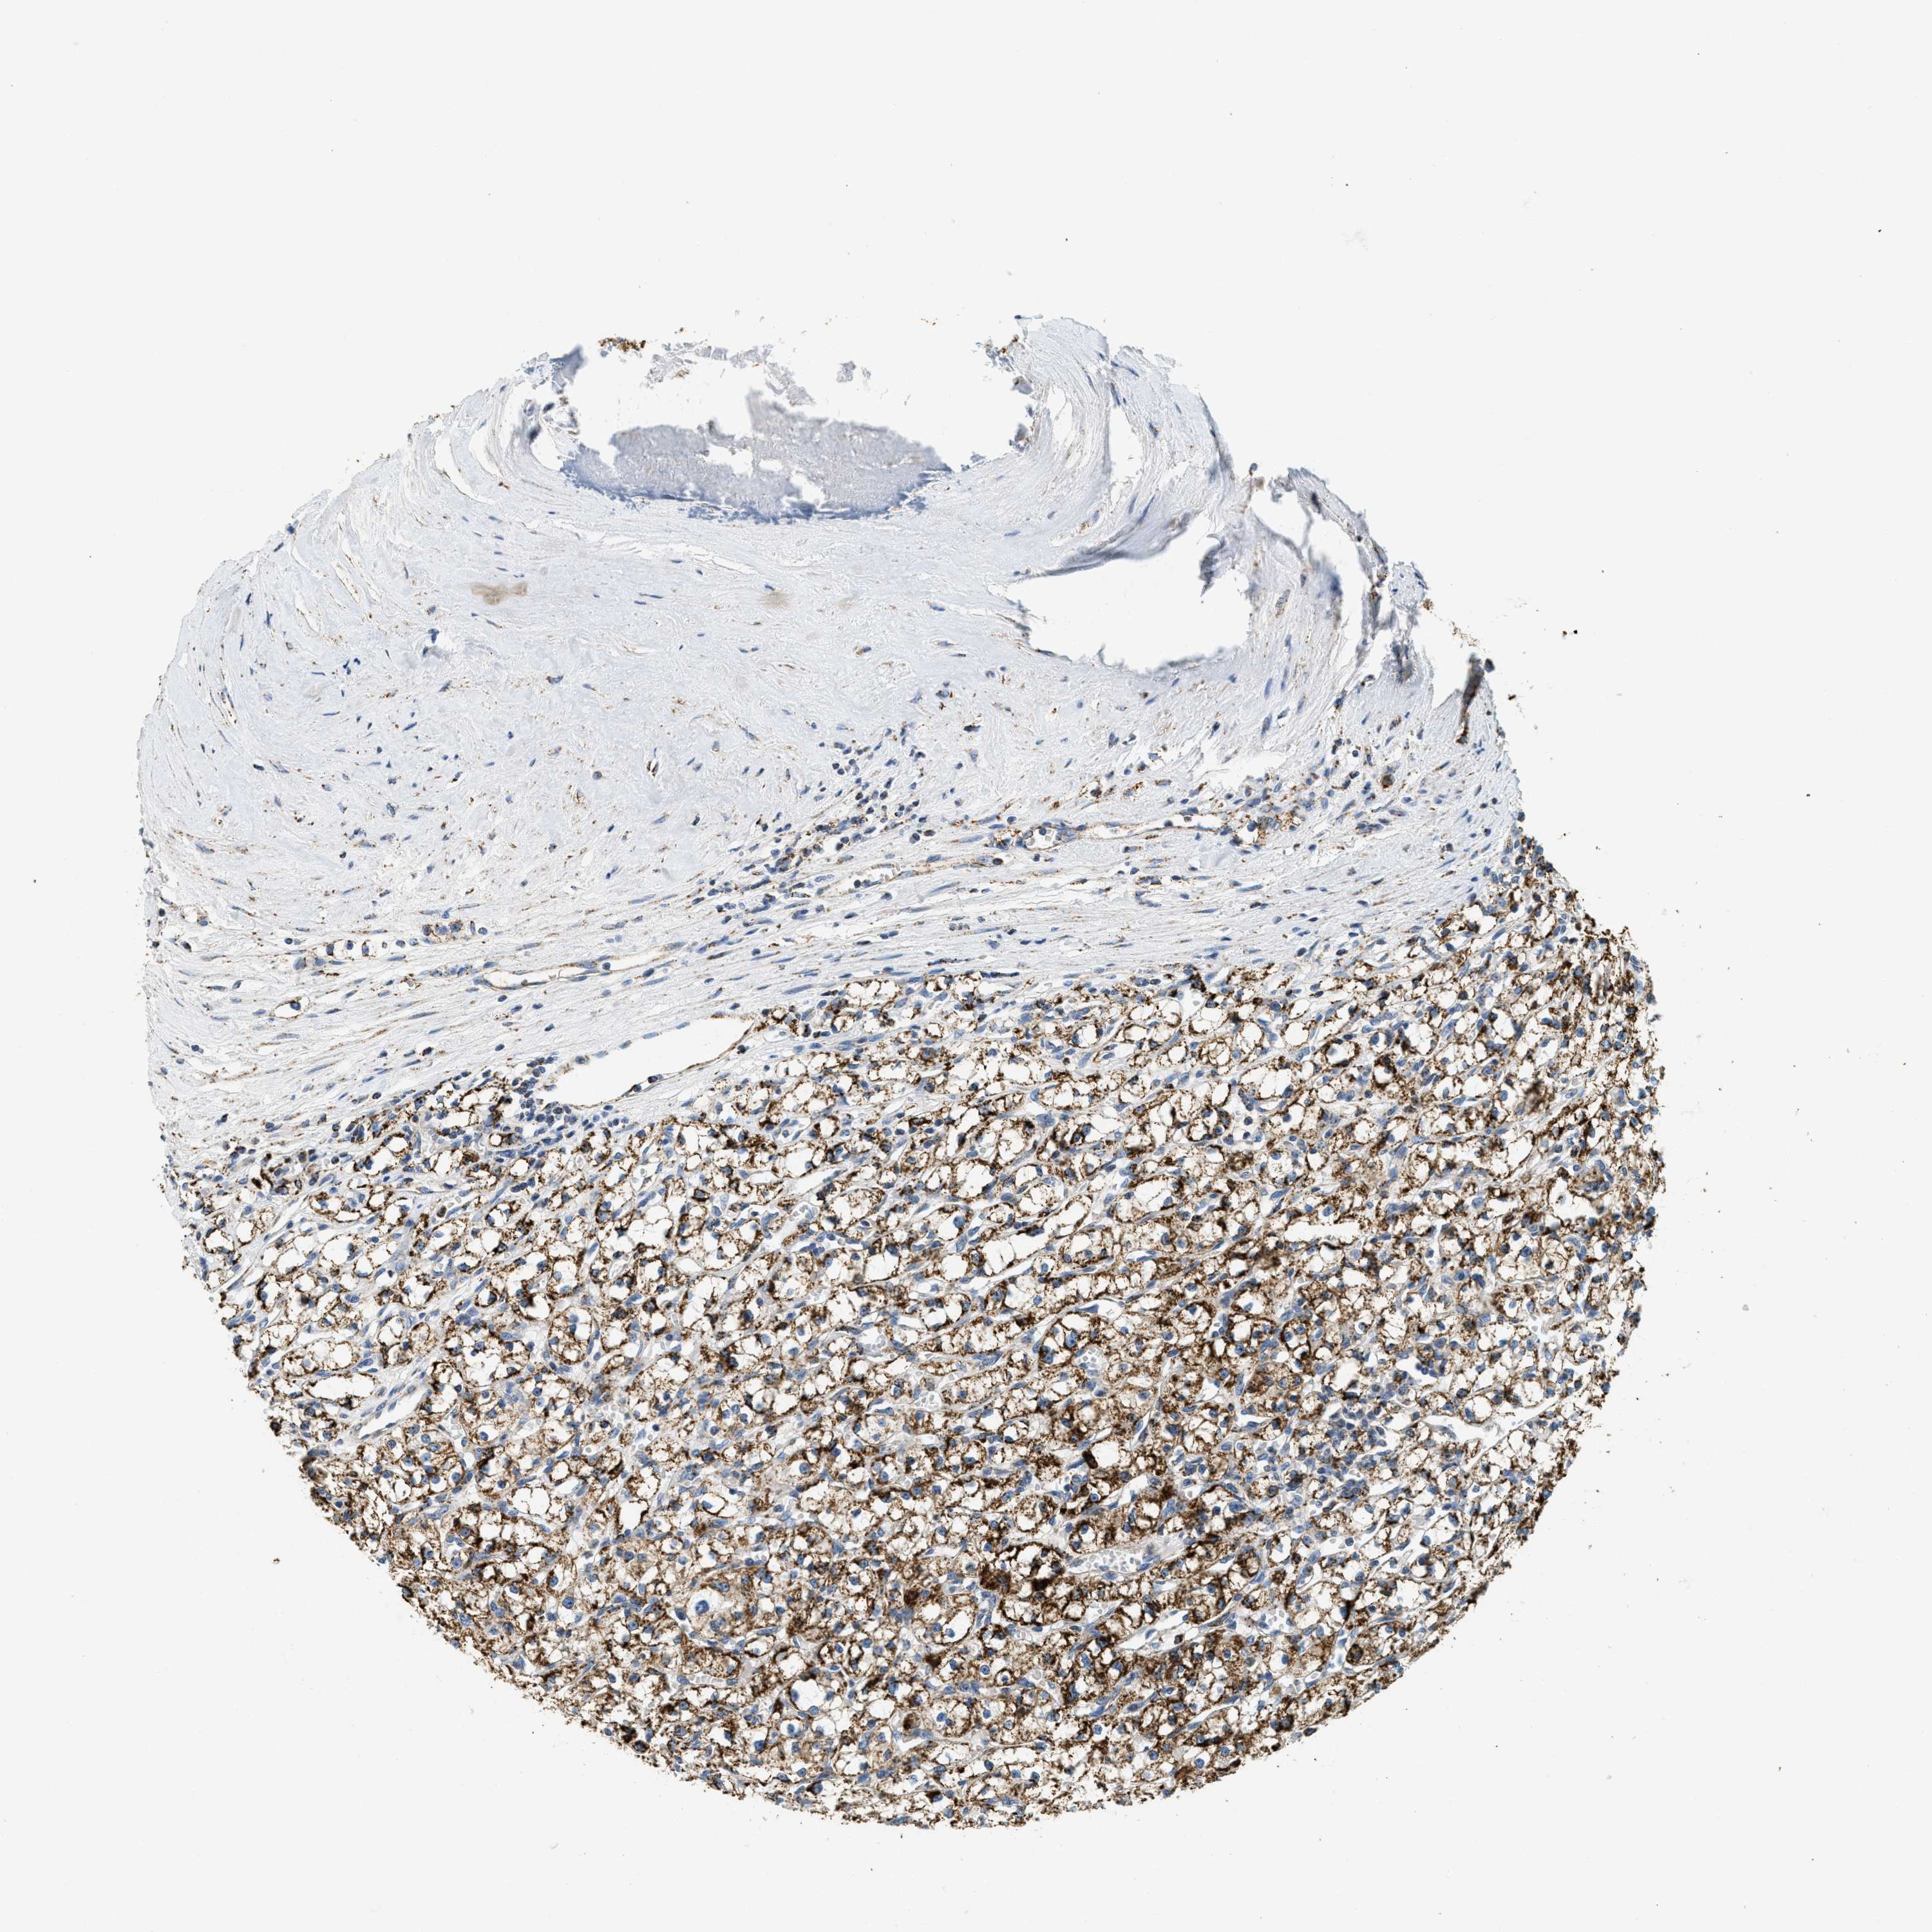

KIDNEY RENAL CLEAR CELL CARCINOMA (TCGA) - Interactive survival scatter ploti

The Survival Scatter plot shows the clinical status (i.e. dead or alive) for all individuals in the patient cohort, based on the same data that underlies the corresponding Kaplan-Meier plots. Patients that are alive at last time for follow-up are shown in blue and patients who have died during the study are shown in red.

The x-axis shows the expression levels (FPKM) of the investigated gene in the tumor tissue at the time of diagnosis. The y-axis shows the follow-up time after diagnosis (years). Both axes are complimented with kernel density curves demonstrating the data density over the axes. The top density plot shows the expression levels (FPKM) distribution among dead (red) and alive patients (blue). The right density plot shows the data density of the survived years of dead patients with high and low expression levels respectively, stratified using the cutoff indicated by the vertical dashed line through the Survival Scatter plot. This cutoff is automatically defined based on the FPKM cutoff that minimizes the p-score. The cutoff can be changed by dragging the vertical line or by entering a cutoff value in the square labeled "Current cut-off".

Under the Survival Scatter plot the p-score landscape (black curve; left axis) is shown together with dead median separation (red curve; right axis). Dead median separation is the difference in median mRNA expression between patients who have died with high and low expression, respectively. It is calculated as follows: median FPKM expression of dead patients with high expression - median FPKM expression of dead patients with low expression. This is intended to aid the user in visually exploring custom cutoffs and the associated p-scores and dead median separation.

Individual patient data is displayed and can be filtered by clicking on one or more of the category buttons on the top of the page. Categories describing expression level and patient information include: high, low, alive, dead, female, male and tumor stages. The scale of the x-axis can be toggled between linear and log-scale by clicking on the "x log" button. Mouse-over function shows TCGA ID, patient information and mRNA expression (FPKM) for each patient.

& Survival analysisi

Kaplan-Meier plots summarize results from analysis of correlation between mRNA expression level and patient survival. Patients were divided based on level of expression into one of the two groups "low" (under cut off) or "high" (over cut off). X-axis shows time for survival (years) and y-axis shows the probability of survival, where 1.0 corresponds to 100 percent.

HLCS is not prognostic in Kidney Renal Clear Cell Carcinoma (TCGA)

TCGA RNA samplesi

RNA-seq data is reported as average FPKM (number Fragments Per Kilobase of exon per Million reads), generated by the The Cancer Genome Atlas (TCGA) .

Normal distribution across the dataset is visualized with box plots, shown as median and 25th and 75th percentiles. Points are displayed as outliers if they are above or below 1.5 times the interquartile range. FPKM values of the individual samples are presented next to the box plot.

Average pTPM 6.5

Number of samples 521